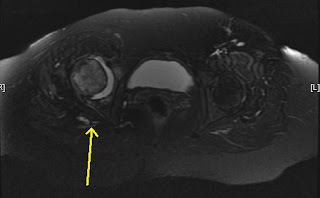

Rheumatoid Arthritis- Hip